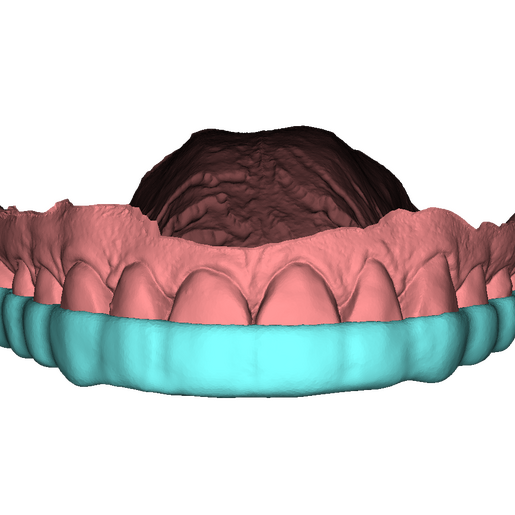

DSD Bite Splint Design

The DSD Bite Splint (night guard) is designed to be worn after a full mouth rehabilitation to protect DSD Natural Restorations and/or DSD Direct composite restorations. The splint design can be used for both milling and printing.

This product is ideal when you need to protect restorations that have already been placed to help avoid possible fractures due to grinding and bruxism.

This is a digital product, delivered in STL format.

An .STL file of the DSD Bite Splint design that can be used for manufacture, either by DSD Lab or your local lab.